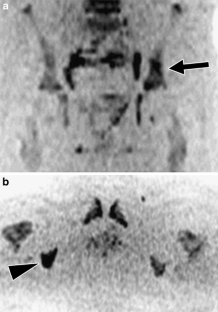

Fig. 3